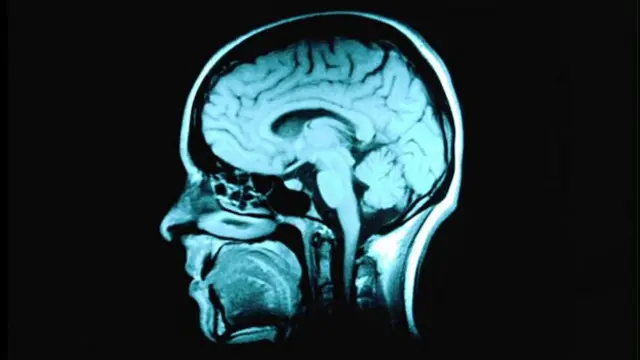

45 के बाद दिमागी क्षमता में कमी शुरु

ताज़ा शोध में पता चला है कि व्यक्ति का दिमाग़ 45 साल की उम्र से ही कमज़ोर होना शुरू हो सकता है.

ब्रिटिश मेडिकल जर्नल में छपे शोध के अनुसार लंदन के यूनिवर्सिटी कॉलेज के शोधकर्ताओं को 45 से 49 साल की आयु वाले पुरुष और महिलाओं की दिमाग़ी क्षमताओं में 3.6 प्रतिशत की गिरावट देखी गई.